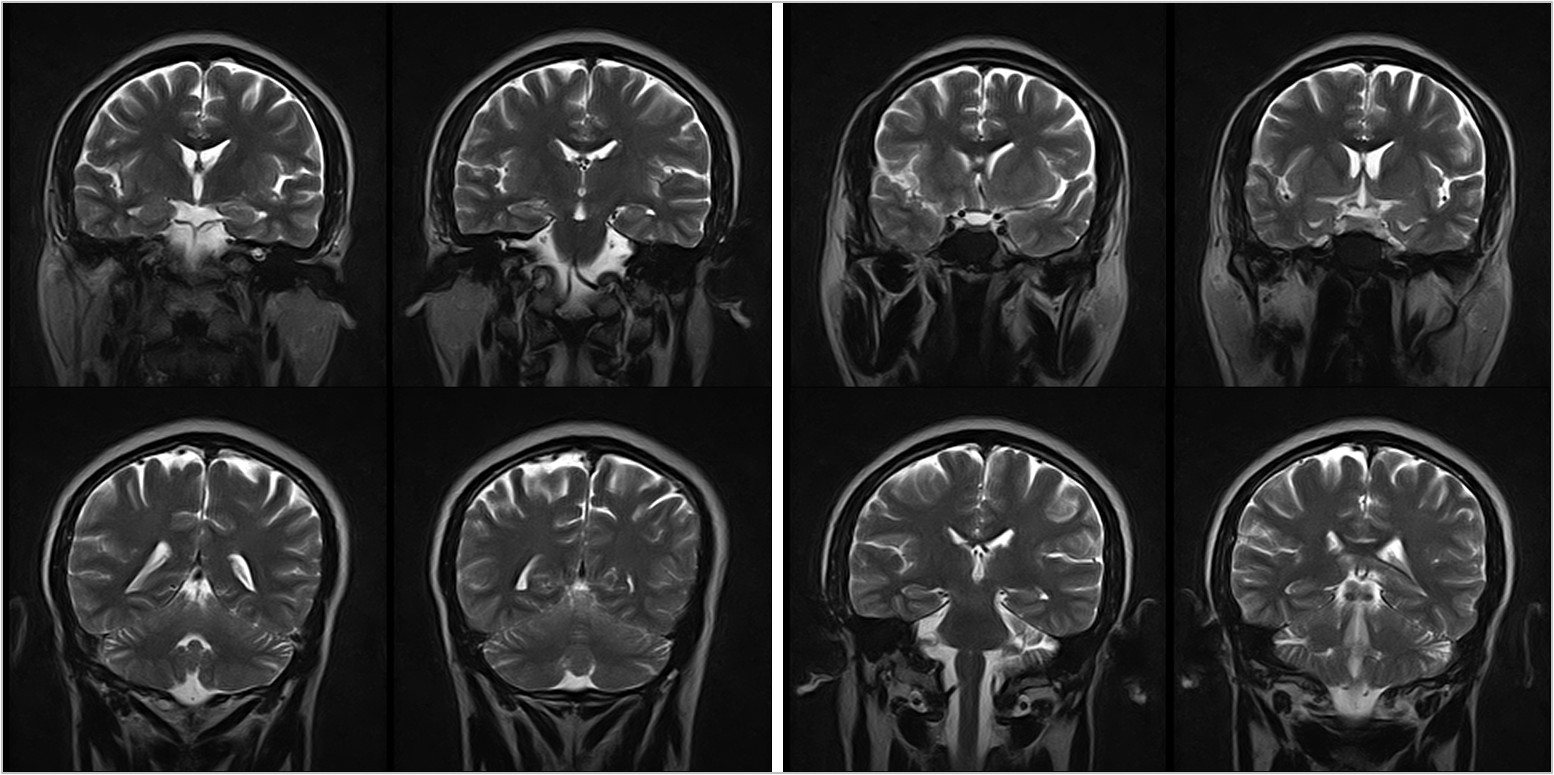

Hình ảnh lâm sàng